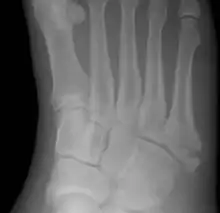

Jones fracture as seen on Xray

The fracture typically occurs when the toes are pointed and the foot bends inwards.[6][2] This movement may occur when changing direction while the heel is off the ground such in dancing, tennis, or basketball.[9][10] Diagnosis is generally suspected based on symptoms and confirmed with X-rays.[3]

Diagnostic x-rays include anteroposterior, oblique, and lateral views and should be made with the foot in full flexion.